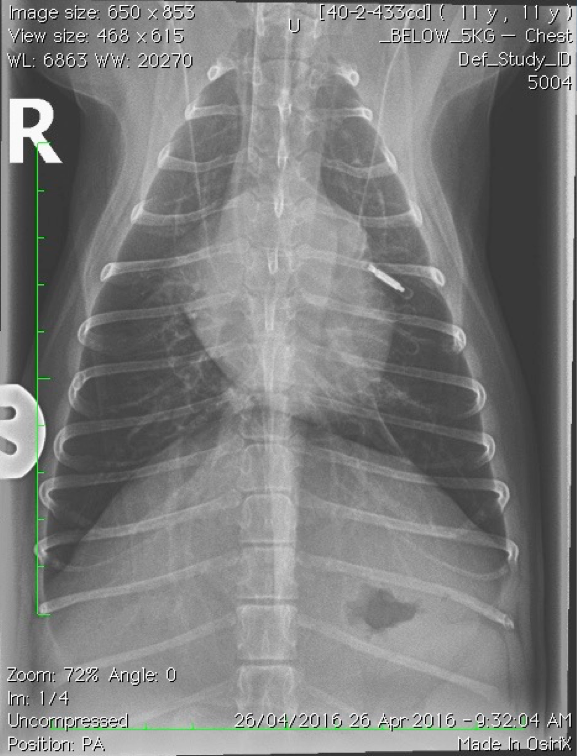

Which lung pattern is shown here?

Alveolar pattern

This pattern creates a soft tissue-like opacity within the lungs; think of it as heavy fog obscuring structures.

There is border obliteration (we can no longer clearly distinguish the cardiac silhouette).

We can still see air bronchograms because alveolar diseases spared the airways.